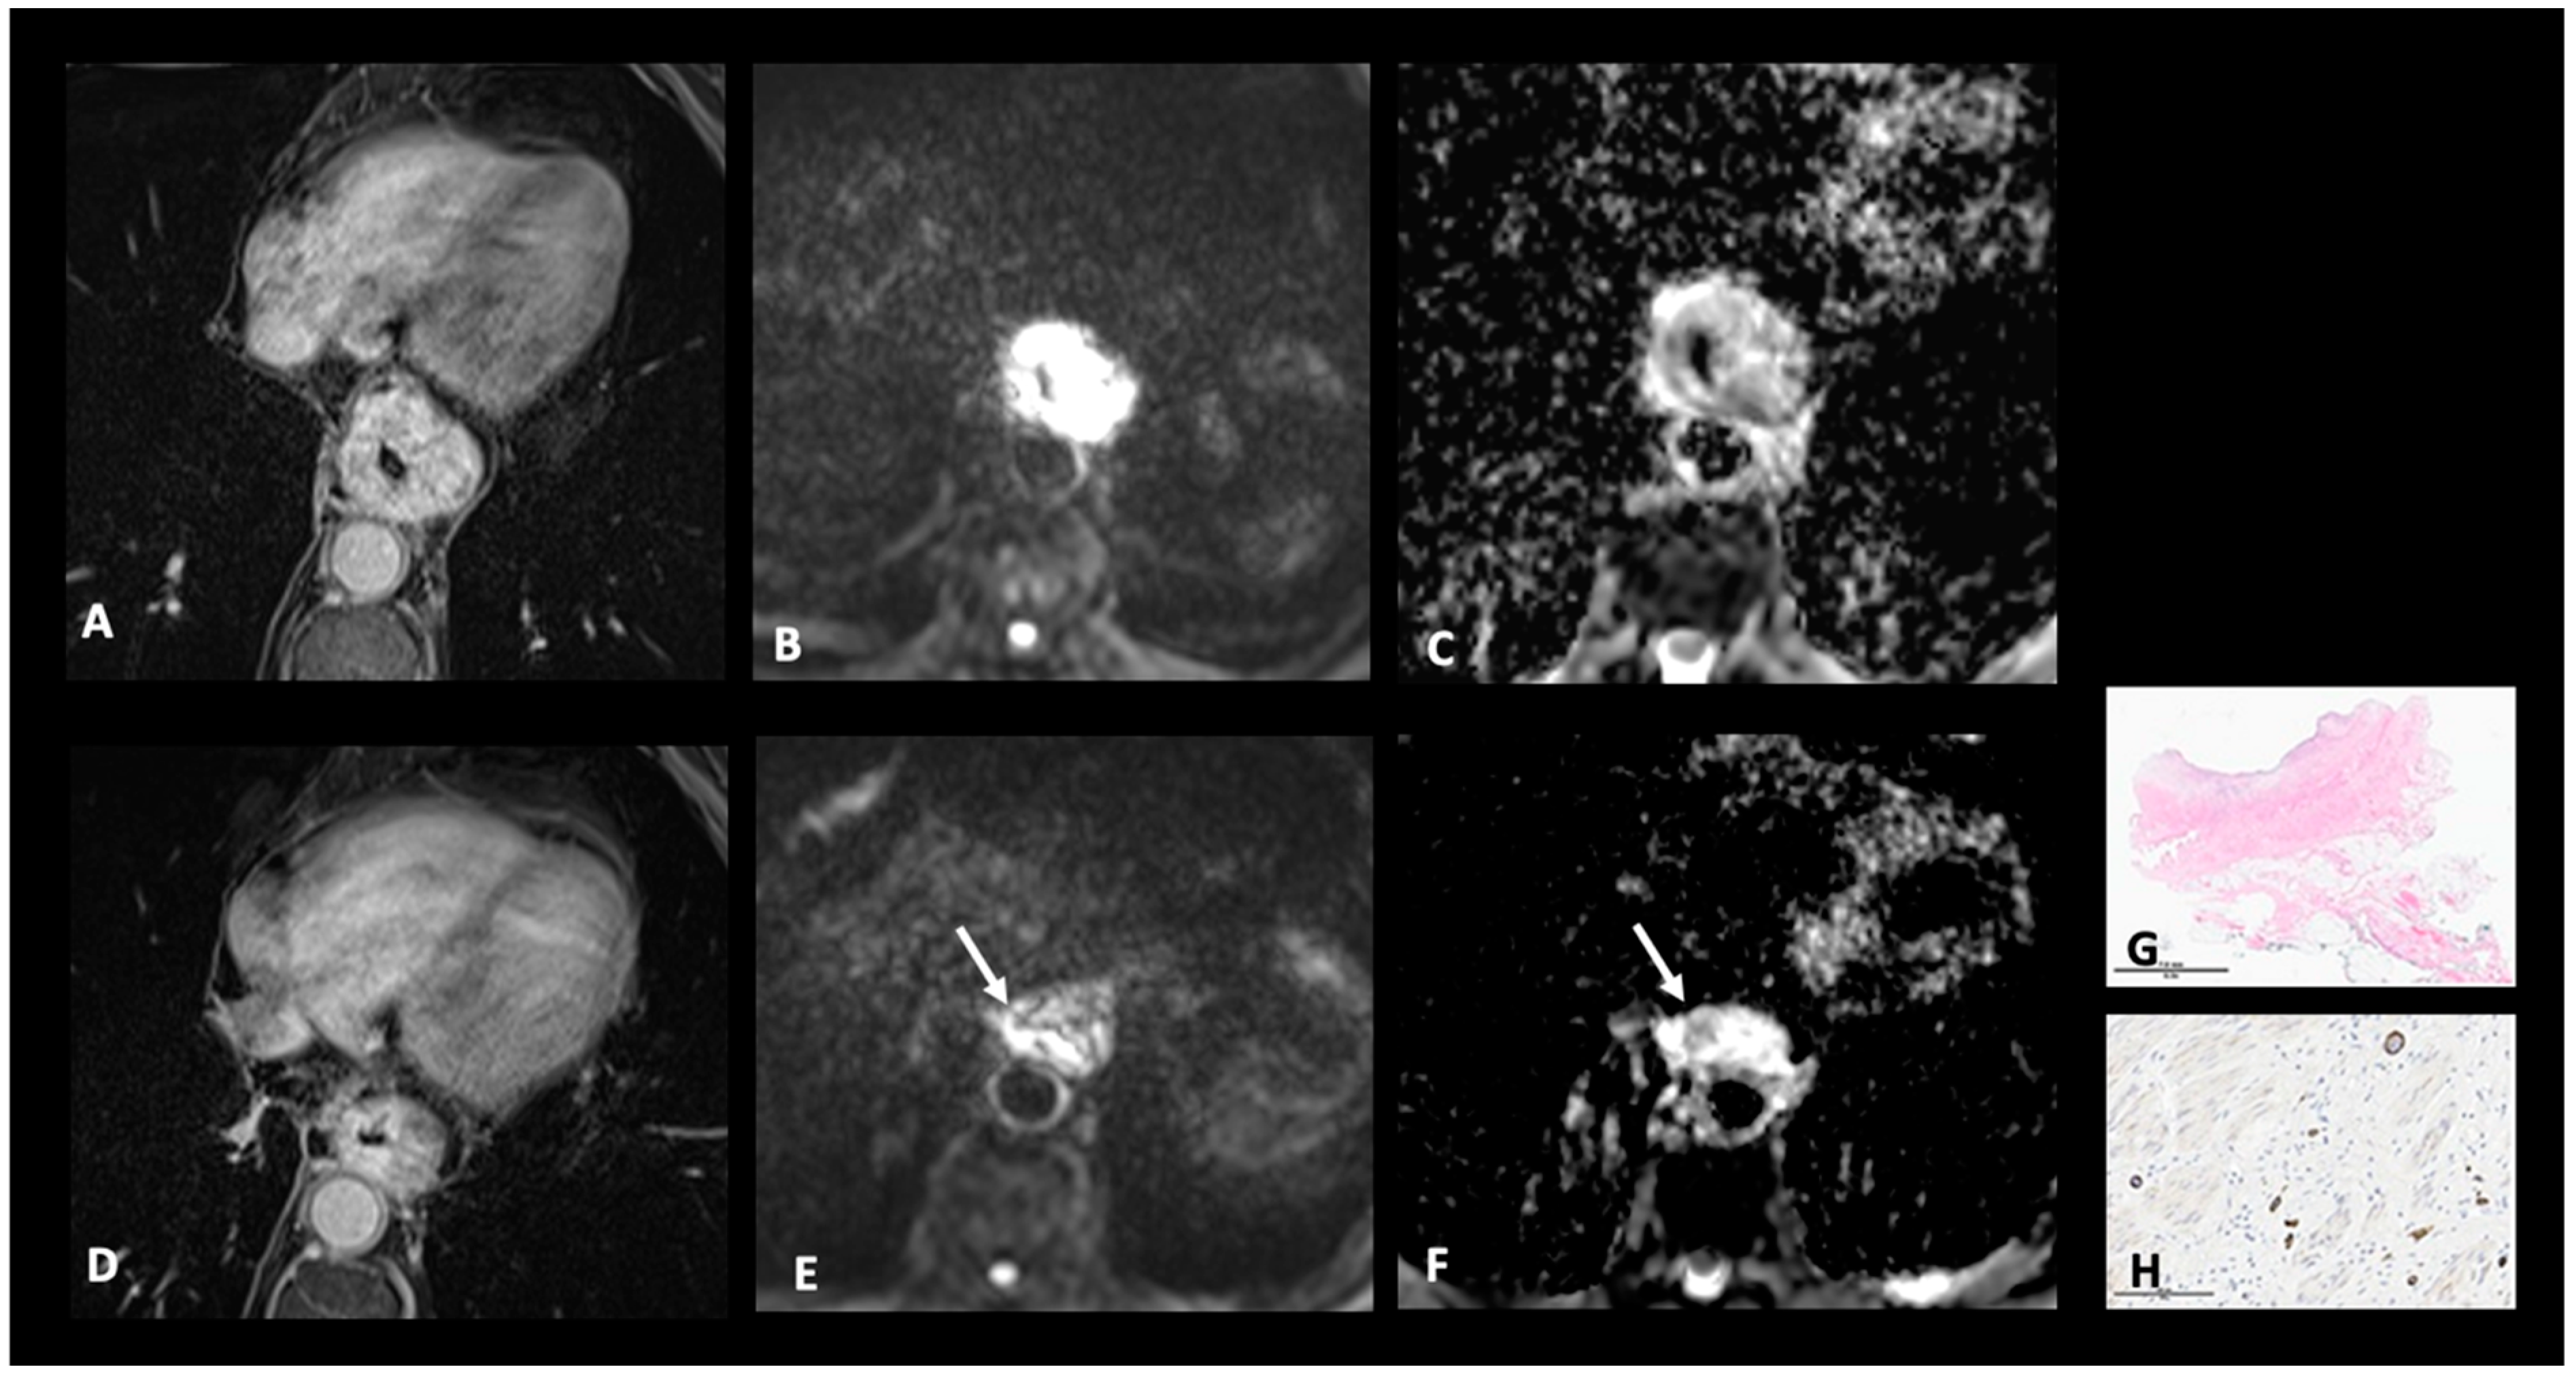

4.1. T Restaging

- Chapellier, P.; Fasquelle, F.; Saglietti, C.; Kinj, R.; Mantziari, S.; Schäfer, M.; Haefliger, L.; Jreige, M.; Vietti Violi, N.; Sempoux, C.; et al. Prospective Evaluation of MR-TRG (Tumor Regression Grade) in Esophageal Cancer after Neo-Adjuvant Therapy: Preliminary Results. Eur. J. Radiol. 2024, 171, 111263. [Google Scholar] [CrossRef]